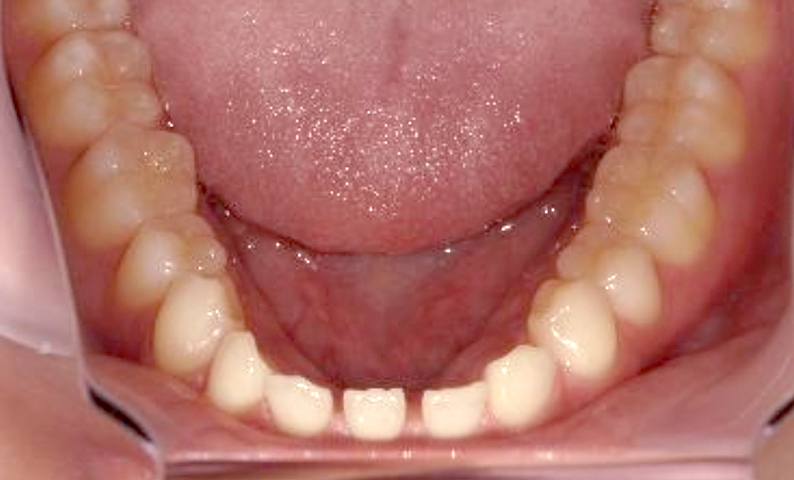

症例_001 前歯「すきっ歯」症例

治療期間:9ヶ月金額:51万円+税20代女性すきっ歯